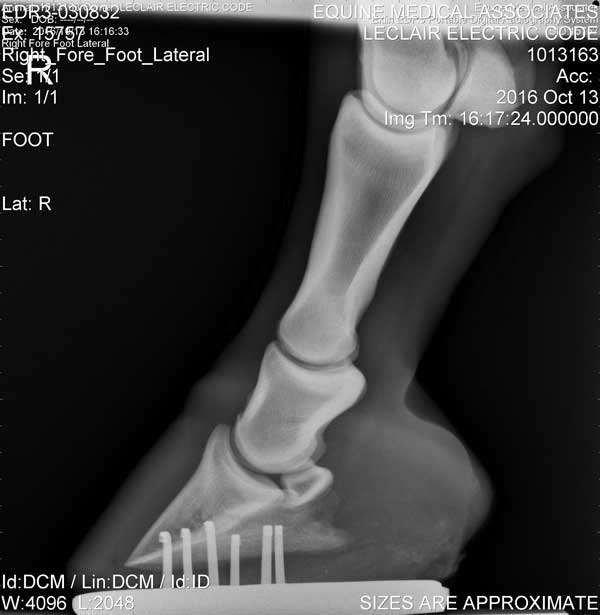

Hoof

Right